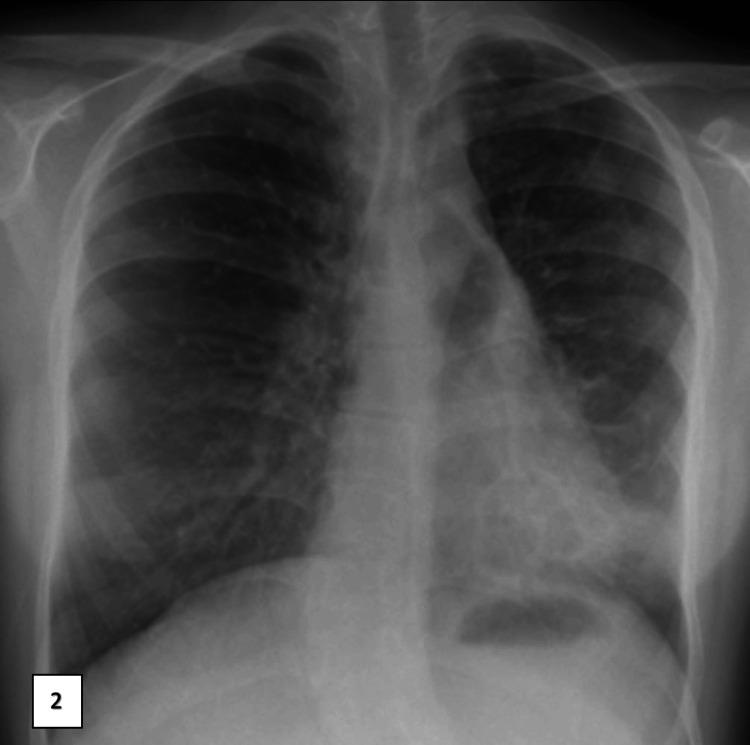

Primary ciliary dyskinesia (PCD) is a heterogeneous autosomal recessive disease marked by organ lateralization in 50% of patients, chronic sinopulmonary disease, infertility in men, and neonatal respiratory distress. Respiratory control cells contain in their apical cytoplasm, which is necessary for the development of multiciliate cells, basal body amplification, and migration. Reduced generation of multiple motile cilia, a rare form of PCD, has been linked to gene abnormalities Individuals with mutations have been reported to suffer from severe lower respiratory infections that cause progressive impairment of lung function. For the first time, we describe the (c.258 262dup.p, Gln88argfs*8 Homozygous) gene mutation in an Indian consanguineous family that resulted in severe PCD.

原发性纤毛运动障碍(PCD)是一种常染色体隐性遗传病,具有异质性,其特征为50%的患者出现器官定位异常、慢性鼻窦肺部疾病、男性不育以及新生儿呼吸窘迫。呼吸控制细胞在其顶端细胞质中含有(某种物质),这对于多纤毛细胞的发育、基体扩增和迁移是必需的。多根活动纤毛生成减少是PCD的一种罕见形式,它与(某个)基因异常有关。据报道,携带(该)基因突变的个体患有严重的下呼吸道感染,可导致肺功能进行性损害。我们首次在一个印度近亲家庭中描述了(某个基因)(c.258 262dup.p,Gln88argfs*8纯合子)基因突变,该突变导致了严重的PCD。